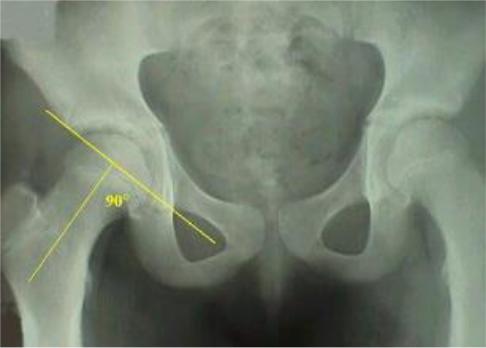

На прямой рентгенограмме тазобедренных суставов определятся проекционный ШДУ (Рис.79), истинный ШДУ (Рис. 80) можно вычислить на рентгенограмме во внутренней ротации нижних конечностей.

Рис. 79. Проекционный ШДУ